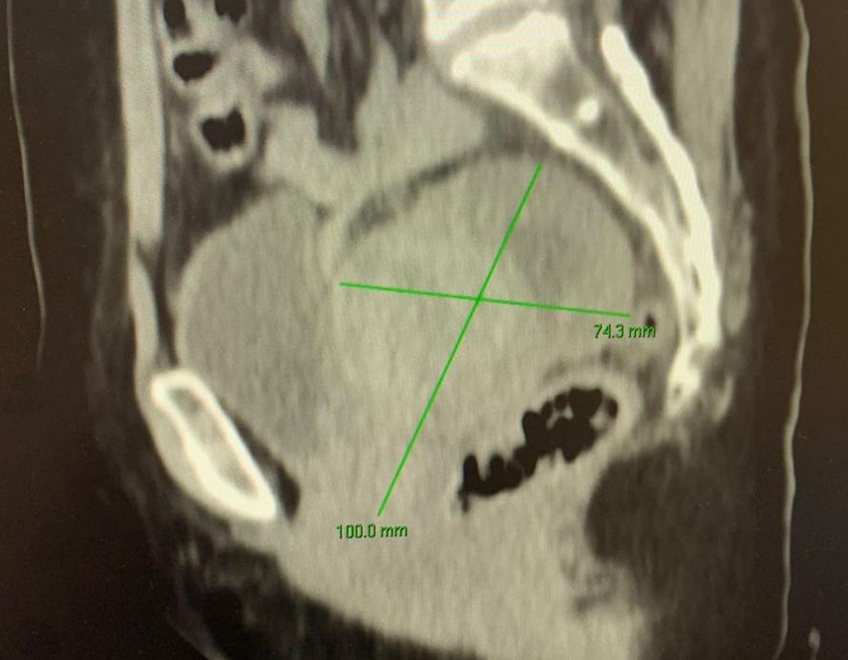

Consulta basada en la prevención, detección oportuna y tratamiento, del Cáncer de mama, ginecológico como Cáncer cervicouterino, ovarios, endometrio, vulva, vagina y enfermedad del trofoblaso.